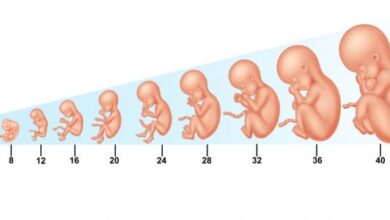

مع بداية الثلث الثاني يكون حجم الجنين ما زال صغيرًا، ومن الجدير بالذكر أنّه بتخطي الشهور الثلاثة الأولى يقل خطر التعرض للإجهاض (بالإنجليزية: Miscarriage)، وتبدأ أعراض الحمل المبكرة التي عانت منها الحامل كالتعب وغثيان الصباح بالاختفاء، وقد تشعر بأنها أكثر نشاطًا فيصبح باستطاعتها ممارسة التمارين الرياضية بعد الرجوع لطبيبها لأخذ المشورة الطبية حول الرياضة المناسبة للحامل عامّةً ولحالتها الصحية خاصةً،[٣] وفيما يأتي بيان هذه المرحلة من الحمل بالتفصيل:

- الأسبوع الرابع عشر: في هذه المرحلة يكون طول الجنين من أعلى رأسه إلى ردفه قد بلغ حوالي 10 سم، ووزنه حوالي 127 غرامًا، ويكون حجمه بحجم حبة درّاقٍ صغيرة، أمّا عن جسمه فيكون مغطّىً بشعر ناعم ورقيق يُسمّى زغب الجنين يوفّر له الدفء، وقد يختفي بحلول موعد الولادة، إضافةً إلى ذلك تتطوّر في هذا الأسبوع بصمات أصابعه بما فيها الإبهام، ويبدأ في ابتلاع كمية صغيرة من السائل الأمنيوسي (بالإنجليزية: Amniotic fluid) فيمرّ خلال المعدة ليبدأ عمل الكلى فتطرح هذا السائل من جديد إلى السائل الأمنيوسي على شكل بول.[٢][٨]

- الأسبوع الثامن عشر: يبلغ وزن الجنين الآن 200 غرام، وطوله من رأسه إلى ردفه 14 سنتيمترًا تقريبًا، وتتجه عيناه أمامًا بينما تأخذ الأذنان مكانهما على جانبي رأسه، ويبدأ جهازه الهضمي بالعمل.[٩]

- الأسبوع العشرين: يشكّل هذا الأسبوع منتصف فترة الحمل؛ إذ يبلغ فيه طول الجنين من رأسه إلى ردفه حوالي 16 سنتيمترًا ويزن أكثر من 320 غرامًا، وتتسارع حركته في هذه المرحلة، وينام ويستيقظ بانتظام، وقد توقظه حركات أمه أو ضوضاء خارجية.[٩]

- الأسبوع الرابع والعشرين: في هذا الأسبوع من الحمل سيبلغ طول الجنين من رأسه إلى ردفه ما يقارب 21 سنتيمترًا، ووزنه أكثر من 630 غرام تقريبًا، كما يكون الجلد أجعد وشفافًا تقريبًا بلون وردي مائل إلى اللون الأحمر؛ نتيجة الدم المرئي في الشعيرات.[١٠]

- الأسبوع السادس والعشرين: قد يبلغ طول الجنين من رأسه إلى ردفه 23 سنتيمترًا ووزنه 820 غرامًا، وستبدأ رئتاه الآن بإنتاج ما يُعرف باسم منشطات السطح أو فاعلات السطح (بالإنجليزية: Surfactant)، وهي المادة التي تسمح للأكياس الهوائية الموجودة في الرئتين بالانتفاخ، وتمنعها من الالتصاق ببعضها عند الانقباض.[١١]

في هذه المرحلة الأخيرة من الحمل سيزداد وزن الجنين بسرعة، وكلّ أسبوعٍ فيها من النموّ سيساعد الجنين على الاستعداد للولادة،[١٢] وفيما يأتي بيان هذه المرحلة بالتفصيل:

- الأسبوع الثامن والعشرين: في هذا الأسبوع قد يبلغ طول الجنين من رأسه إلى ردفه 25.4 سنتيمترًا، ووزنه ما يقارب 1.13 كيلوغرامًا، وتصبح عيناه مفتوحتين جزئيًا.[١٣]

- الأسبوع الثلاثون: في هذا الأسبوع سيبلغ طول الجنين من رأسه إلى ردفه أكثر من 27 سنتيمترًا، ووزنه 1.3 كيلو جرامًا تقريبًا، وستبدأ خلايا الدم الحمراء بالتكون في نخاعه العظمي، وستصبح رئتاه قادرتين على التنفس، لكنهما قد تحتاجان إلى المساعدة الطبية خارج الرحم، لذلك سيبقى جميع الأجنّة الذين يولدون في هذه الفترة تقريبًا على قيد الحياة إذا تلقّوا خدمات العناية المركزة، وإضافةً إلى ذلك ستزداد كثافة شعر رأس الجنين، وسيتمكّن من البكاء وفتح عينيه بالكامل.[١١][١٣]

- الأسبوع الثاني والثلاثين: سيبلغ طول الجنين من رأسه إلى ردفه 28 سنتيمترًا، ووزنه 1.7 كيلوجرامًا تقريبًا، وسيبدأ الزغب الذي غطى جسمه بالتساقط، وستظهر أظافر قدميه.[١١]

- الأسبوع الرابع والثلاثون: يبلغ طول الجنين الآن 30 سنتيمترًا تقريبًا، ويزن حوالي 2 كيلوغرامًا، وتكون أظافره بلغت أطراف أصابعه، وجلده ناعم ووردي.[١٣]

- الأسبوع السادس والثلاثين: يبلغ طول الجنين من رأسه إلى ردفه حوالي 31.7 سنتيمترًا، ووزنه 2.5 كيلوغرامًا تقريبًا، أمّا حركته فبدأت تصعب، إذ يحتلّ جسمه معظم الكيس الأمنيوسي داخل الرحم، ولكن مع ذلك قد تشعر الأم بكثيرٍ من حركاته.[٩][١٣]

- الأسبوع السابع والثلاثين: يكون الجنين الآن مستعدًا للولادة، ويبلغ طوله من رأسه إلى كعبه حوالي 48.6 سنتيمترًا، ووزنه أكثر من 2.9 كيلوغرامًا، قد يبدأ رأسه بالنزول إلى الحوض استعدادًا للولادة فيما يُعرف بنزول الجنين، حتى الآن لا يزال جهازه الهضمي في طور النمو، وسيستمر نموّه لعدة سنوات بعد ولادته، ويُشار إلى اكتمال طول أظافر قدميه، إضافةً إلى استمرار حركة عضلات وجهه فيستطيع العبوس، أمّا حاسة السمع لديه فأصبحت الآن أكثر حساسية، إذ تلاحظ الأم حركاته استجابةً لأصوات معينة، ويُشار إلى ضرورة مراجعة الطبيب في حال لاحظت الحامل تغيّرًا لنمط حركته عن المعتاد.[٩][١٤]

- الأسبوع الثامن والثلاثين: قد يكون وزن الجنين أكثر من 2.9 كيلوغرامًا، وجزء كبير من هذا الوزن عبارة عن طبقة من الدهون تساهم في بقائه دافئًا عندما يخرج من الرحم، وتنشط ردود فعله كقبض اليدين والمص، ممّا يساعده على الرضاعة لاحقًا، أمّا أعضاؤه فجميعها تعمل؛ إذ إنّ الدماغ الآن بدأ في السيطرة على كامل وظائف الجسم بما فيها عملية التنفس وتنظيم نبض القلب، لكن في المقابل تباطأ معدل نموّه.[٢]

- الأسبوع التاسع والثلاثين: يبلغ طول الجنين من رأسه إلى كعبه 50.7 سنتيميترًا، ويزن أكثر من 3.3 كيلوغرامًا، وفي هذا الأسبوع يزداد سمك جلده ويصبح باهتًا، ويُشار إلى أنّ الرئتين ستنتجان المزيد من منشطات السطح، وبذلك يصبح الطفل مستعدًا للتنفس خارج الرحم.[١٥]

- الأسبوع الأربعون: يعدّ هذا الأسبوع هو الموعد المُتوقع للولادة، ويكون الجنين بكامل حجمه ويُقدّر بمتوسط 50.8 سنتيمترًا طولًا، و 3.2 كيلوغرامًا تقريبًا، ولكن يُشار إلى أنّ هذه تبقى تقديرات ويوجد اختلاف بأحجام حديثي الولادة، وكذلك الأمر بالنسبة لموعد الولادة الذي قد يتأخر في بعض الحالات عن موعده المحدد، لذلك يُنصح حينها بمراجعة الطبيب لتحديد الإجراء المناسب.[٢]